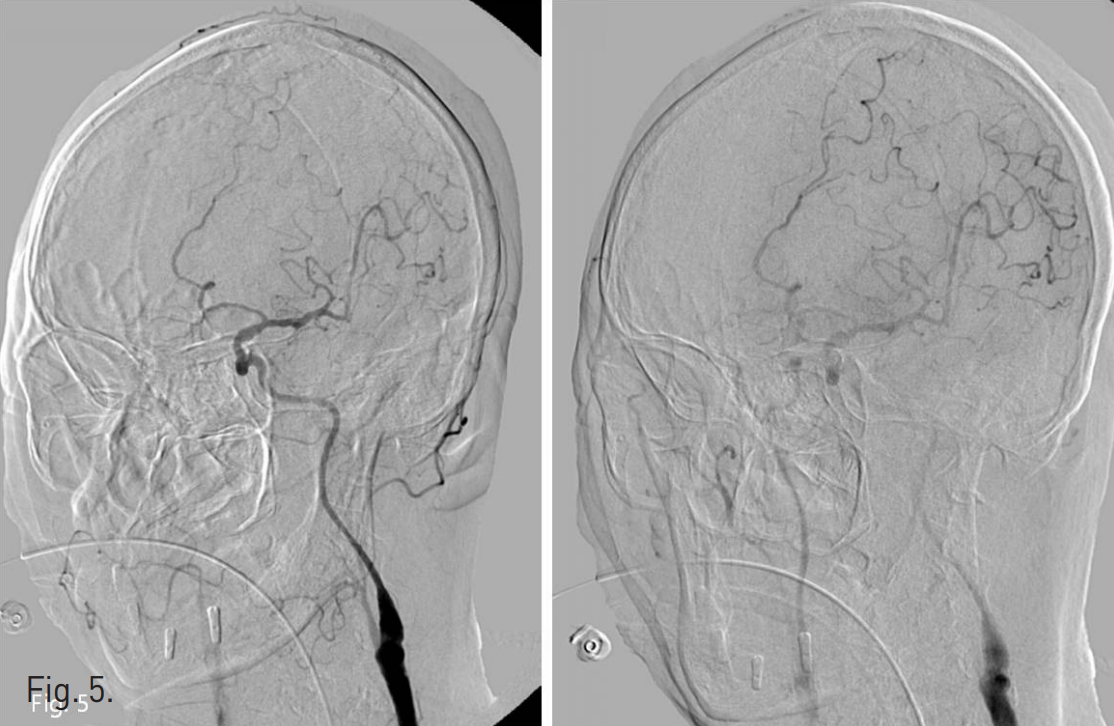

우측 넙다리 동맥을 통해 우측 무명동맥 조영술을 시행하였다. 우측 총경동맥 기시부에서 약 1.0cm 이내인 총경동맥 근위부 좌상방으로 국소적인 돌출부위가 있고 이 부위에서 기관 절개부위로 조영제가 새는 소견이 있었다(Fig. 2B). Sim-1 catheter(Cook, Bloomington, USA)로 selection하고 stiff guidewire(Radifocus, Terumo, Japan)로 교체한 뒤, stiff guidewire tip은 외경동맥 분지인 후두동맥에 위치시키고 8F guiding catheter(Cordis, FL, USA)를 우측 총경동맥 중간부위까지 삽입하고, 8mm diameter를 가진 vascular plug device(AMPLATZER® Vascular Plug II, AGA Medical Corp., Golden Valley, MN)를 총경동맥 기시부에서 무명동맥으로 빠져 나오지 않도록 guiding catheter를 빼면서 총경동맥의 최대한 하방에 설치하였다. 처음 10여 분 동안에는 출혈이 멈추었으나 동맥 박동에 의해 조금씩 plug device가 상방으로 이동하면서 조영제가 조금 새는 모양을 보여서 추가적인 plug device 또는 8mm 직경의 Micronester coil을 설치하려 하였으나 공간이 충분치 않았다(Fig. 3). Plug device의 하내방에 있는 출혈부위를 microcatheter와 microwire(Renegade™, Transend, Boston scientific, Watertown, MA)로 selection 하여 3-2mm 크기의 microcoil(VortX, Boston scientific, Watertown, MA) 두 개를 fistula tract 내부에서 총경동맥 내강으로 튀어 나올 정도의 위치에 정확히 떨어지도록 설치하였고, 이후에는 더 이상 출혈이 발생하지 않았다(Fig. 4). 약 10분 후에 시행한 좌측 경동맥 조영술상 출혈은 없고, 곁동맥들을 통해 상방의 우측 경동맥이 조영되는 것을 확인하고 시술을 마쳤다(Fig. 5). 시술 일주일 후까지 출혈은 없어 퇴원하였으며 퇴원시 혈압은 100/70mmHg, 맥박 92회/min, Hemoglobin 수치는 11.4g/dL, WBC는 10,600/uL이었다.

Fig. 5

Left common carotid arteriography shows good contrast filling of right carotid arteries through extracranial and intracranial collaterals.